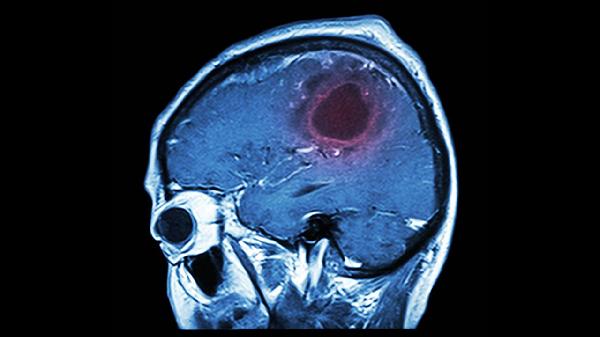

脑血栓伴有失眠可通过中药调理,常用药物有安宫牛黄丸、复方丹参片、天麻钩藤颗粒、酸枣仁汤、柏子养心丸等。脑血栓多因气血瘀滞、痰浊阻络所致,失眠常与心神失养或肝阳上亢相关,需在中医师辨证后选择活血化瘀、安神定志类方药。